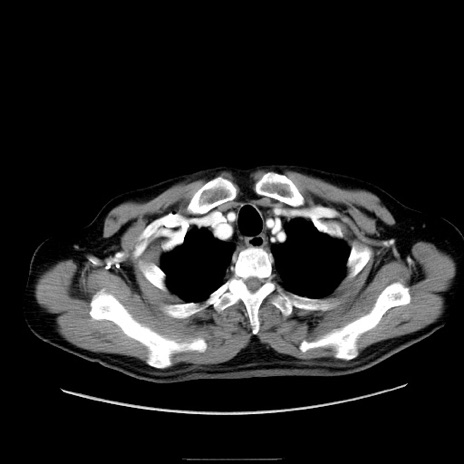

冠状断像